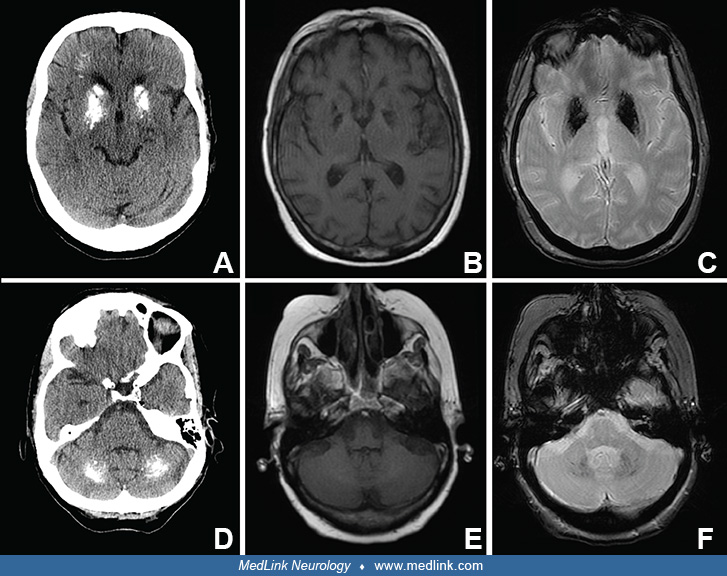

From www.medlink.com

Idiopathic basal ganglia calcification (IBGC) MedLink Neurology Basal Ganglia Calcification Young Cerebellar, dentate, and thalamic calcification may occur, as may calcification of the leptomeningeal vessels. It can potentially cause a variety of neurological symptoms and can affect mood, perceptions, and behavior. Typically, there is symmetrical basal ganglia rock or spot calcification, with or without deep gyral calcification. Familial idiopathic basal ganglia calcification (ibgc) or fahr’s disease is a rare neurodegenerative disorder. Basal Ganglia Calcification Young.